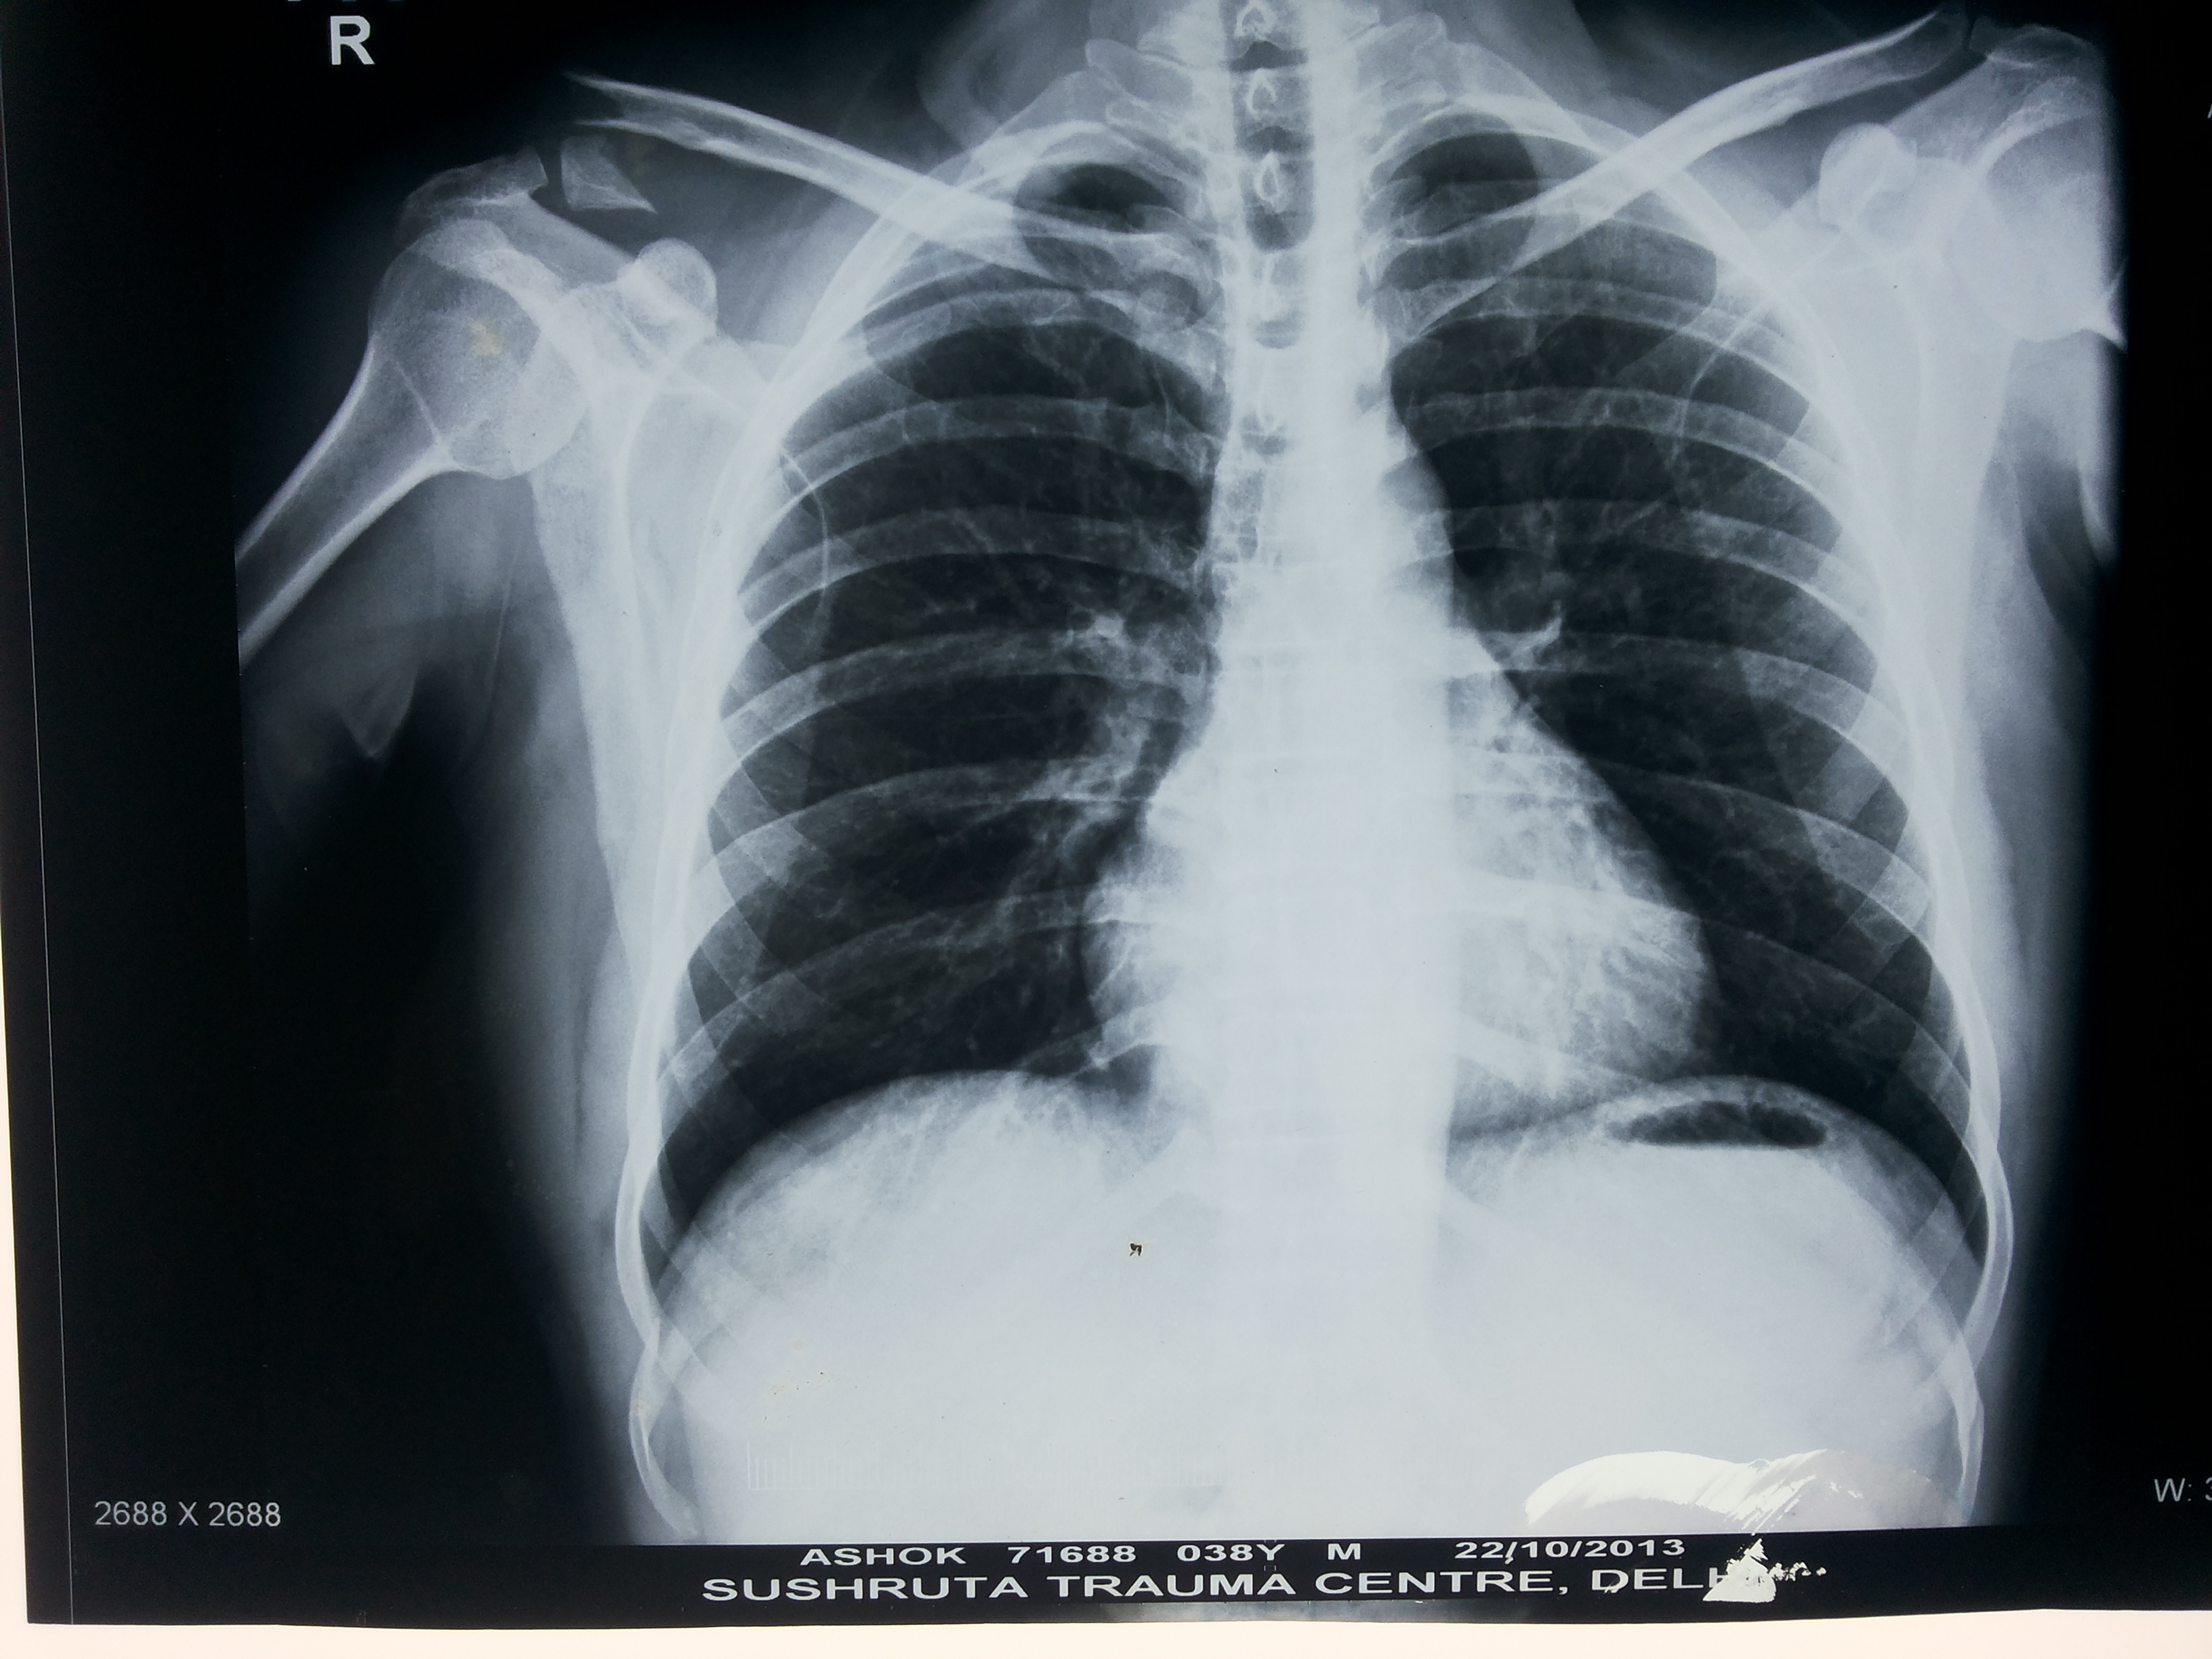

A comprehensive physical examination of the shoulder along with a detailed history and a series of x-rays will lead to a confirmed AC joint injury diagnosis. An x-ray can also help rule out any additional injuries to the bone, such as a fracture of the end of the collarbone. In addition to x-ray, an MRI scan to determine the injury grade and assess injury of surrounding ligaments to arrive at an effective and individualized treatment plan.

Imaging including x-rays and MRI (magnetic resonance imaging) are frequently used as well. X-rays can help make sure that the shoulder is located within the socket, and evaluate for any fractures. MRI can be used to determine if there are any injuries to the soft-tissues surrounding the shoulder, including the labrum. Based on all of the information gathered from the history, physical exam, and imaging, Doctor can discuss treatment options based on your goals and activity level.

Medical imaging can also be done to look at the severity of the shoulder arthritis and rule out other possible causes of pain. An X-ray of your shoulder can show if there is a loss of space between the shoulder head and the glenoid, or “socket.” A loss of joint space means there is a loss of cartilage. If X-rays do not give a clear cause, an MRI can also be done.